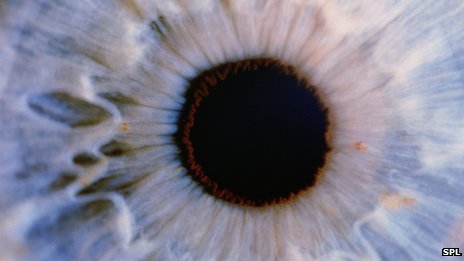

在試驗(yàn)中,來自牛津大學(xué)的研究小組選擇了完全失明的老鼠作為研究對(duì)象。這些老鼠的視網(wǎng)膜中完全沒有感光細(xì)胞,無法判斷光明和黑暗。

在注入感光細(xì)胞后,研究人員不斷觀察這些老鼠能否感受到亮光,檢測(cè)在遇到亮光時(shí)它們的瞳孔是否會(huì)收縮,并用腦部掃描儀觀察老鼠的腦部是否處理視覺信息。結(jié)果顯示,接受試驗(yàn)的老鼠在兩周后視力便有所恢復(fù)。